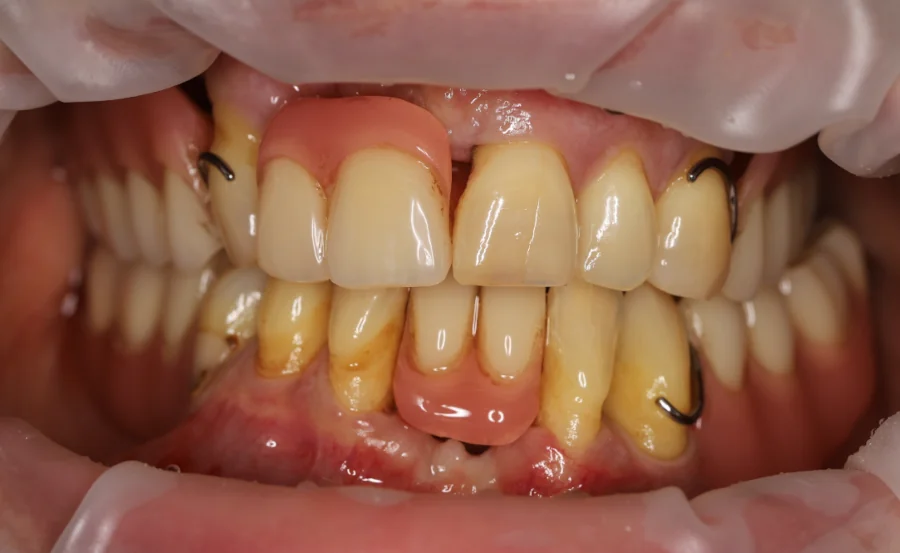

Die Patientin stellte sich mit fortgeschrittener Parodontitis und stark abgenutzten Zähnen durch Bruxismus vor. Sie wünschte sich wieder schöne Zähne, eine stabile Kaufunktion und ein natürlich wirkendes Lächeln.

Behandlungsmaßnahmen: Laserunterstützte Zahnreinigung bei Parodontitis, Setzen von 5 Zahnimplantaten in den Seitenbereichen von Ober- und Unterkiefer, Bruxismus-Therapie mit Botulinumtoxin sowie Zahnkronen in beiden Kiefern. Die Vollkeramik-Zahnkrone Vorher Nachher Bilder zeigen die deutliche Verbesserung von Funktion, Ästhetik und Komfort.